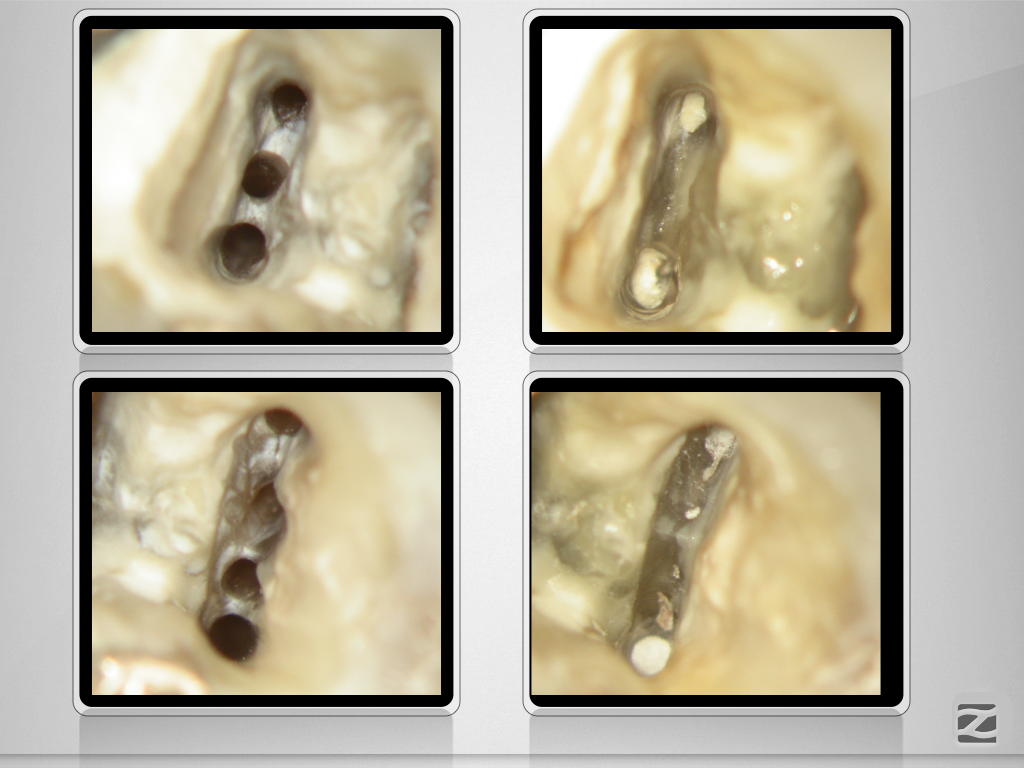

36D.007

7 auf einen Streich